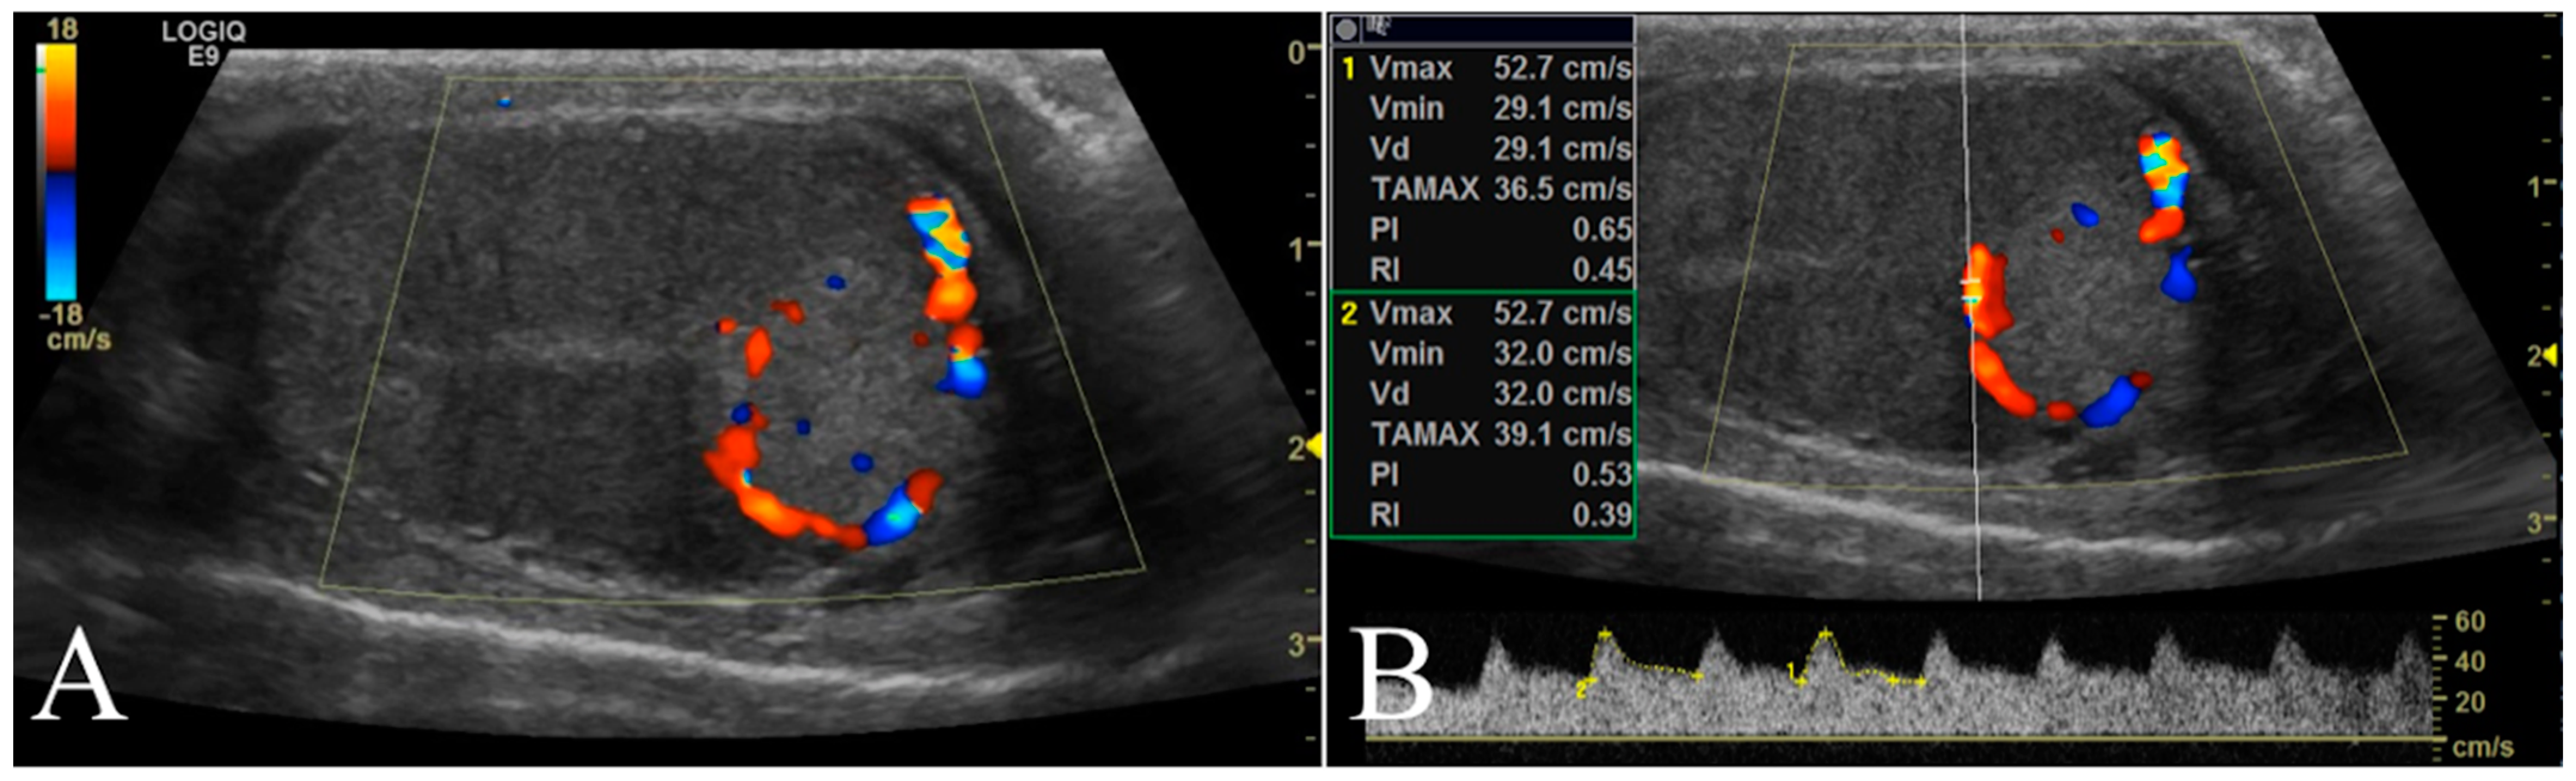

2.4. B-Flow Examination

B-flow examination was focused of the vascularization on the testicular tumor lesions. Once testicular parenchyma was visualized by B-mode, the system was switched to B-flow. Still images and video clips were saved for each location examined for subsequent analyses. The vessels of the tumor lesions were scored as 0, 1, or 2 if absent, smaller, or larger than 2 mm in diameter, respectively. Moreover, the vascularization was classified as P if the vessels were perilesional or I if distributed within the tumor lesion (Figure 3).

Figure 3. Conventional ultrasonographic scans (left panels) of two different seminomas found respectively in the right testicle of a 10 year old Labrador Retriever in (A) and in the right testicle of a 9.5 year old German shepherd in (B). In the right panel the B-flow images show the I distribution of the lesional vessels (arrow) scored as 2 in (A), while in (B) it was possible to record the P pattern of vessels distribution (arrows) scored in this case as 1. In this B-flow image, it is also possible to visualize some physiological testicular vessels (arrows head), represented by the marginal region and intra-testicular branches of testicular artery.